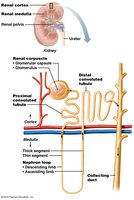

Anatomy of the Kidney

Gross Structure and Blood Flow

The kidneys are retroperitoneal organs located in the abdominal cavity, protected by connective tissue and adipose layers. Each kidney contains about 1.2 million nephrons, the functional units responsible for urine formation.

Renal Cortex: Outer region containing most nephrons.

Renal Medulla: Inner region with renal pyramids and loops of Henle.

Renal Pelvis: Funnel-shaped structure collecting urine into the ureter.

Blood Supply: Kidneys are highly vascularized, receiving about 20% of cardiac output.

The Nephron

Types and Structure

Nephrons are the microscopic functional units of the kidney. There are two main types:

Cortical Nephrons: 85% of nephrons; located mostly in the cortex.

Juxtamedullary Nephrons: 15%; loops of Henle extend deep into the medulla, crucial for concentrating urine.

Nephron Components

Renal Corpuscle: Includes the glomerulus (fenestrated capillary bed) and Bowman’s capsule (with podocytes forming filtration slits).

Renal Tubules: Proximal convoluted tubule (PCT), loop of Henle, distal convoluted tubule (DCT), and collecting duct.